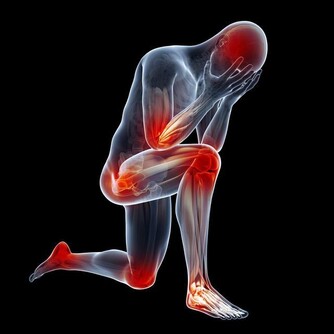

3. 腰酸腿軟

坐著看電視、用電腦或開車超過2小時就感到腰酸。或是在廚房做飯站立超過1小時,就兩腿發軟。

4. 乏力

手不提重物,爬到3樓就兩腿發軟、四肢乏力。